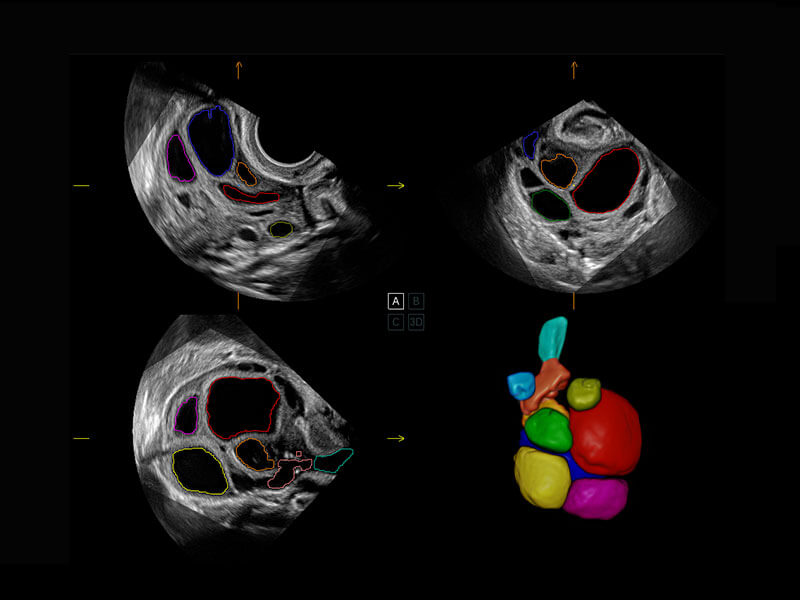

胎心筛查

P60搭载一系列胎儿心脏成像技术,实现精细的胎儿心脏评估。

• 胎心容积成像